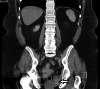

Aggressive angiomyxoma is a rare mesenchymal tumour, primarily arising in the soft tissue of the pelvis and perineum in women of reproductive age. There is a paucity of evidence on optimal management because of the rarity of these tumours, but the consensus has been for surgical excision. We present the case of a 65-year-old woman who was admitted with left-sided buttock pain and initially diagnosed with a perianal abscess. She underwent examination under anaesthesia rectum with surgical excision of the lesion, subsequent histopathological and immunochemical analysis was suggestive of aggressive angiomyxoma. To complement our case report, we also present a literature review focusing on aggressive angiomyxoma in the ischioanal fossa (also known as the ischiorectal fossa) with only eight cases of primary aggressive angiomyxoma involving the ischioanal fossa documented to date. The primary aims of this case report and literature review are to familiarise clinicians with the clinical, histopathological and immunochemical features of these tumours, and to increase appreciation that despite the rarity of aggressive angiomyxoma, it might be considered in the differential diagnosis of ischioanal lesions.